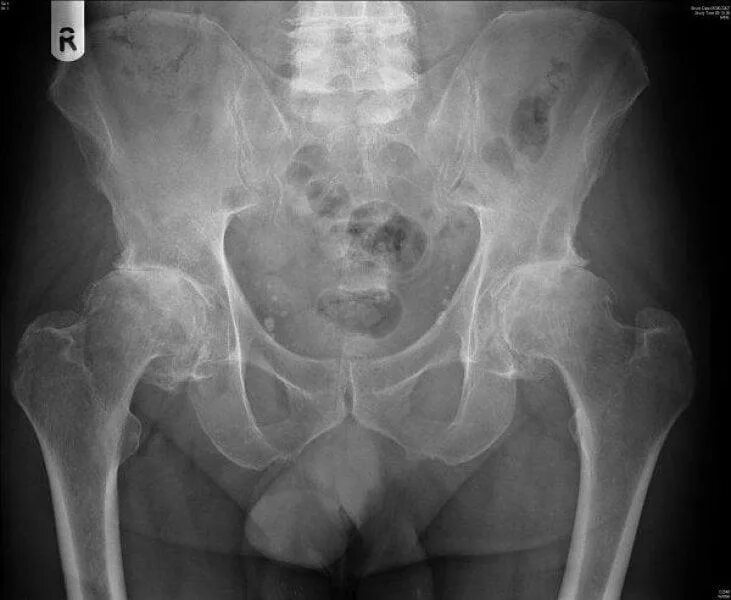

Коксартроз тазобедренного сустава 1 2